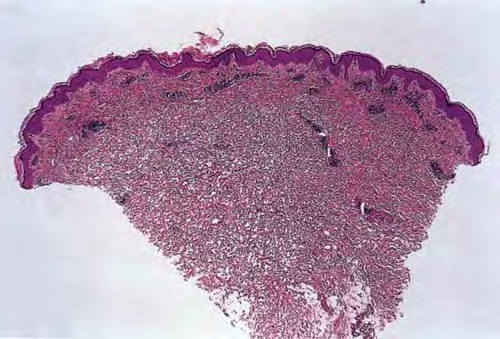

Classic pruritic urticarial papules and plaques of pregnancy (PUPPP) reveals papules within prominent striae distensae . Erythematous urticarial papules and plaques of the trunk and extremities also are observed, although the periumbilical area is spared. Small vesicles often are noted, but larger bullae do not occur and would suggest the more rare herpes gestationis. Less commonly, target lesions and annular and polycyclic wheals may be present. PUPPP usually does not affect the face, palms, or soles. Although the eruption is intensely pruritic, excoriations rarely are found. One report describes a case of PUPPP that progressed to involve the neck, arms, and legs in a photosensitive distribution as the initial abdominal involvement settled.5